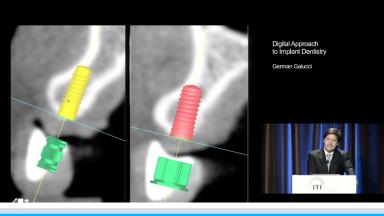

Digital Approach to Implant Dentistry

The aim of this lecture is to take the viewer through the digital workflow, from treatment planning to the reconstructive phase. Superimposing DICOM and STL files in an appropriate software allows for precise planning of the implant treatment and production of the surgical stent. For the surgical stent to be accurate, it must be properly seated; this lecture addresses in detail how to produce a precise stent in most demanding cases - edentulous patients. Furthermore, it takes us through the steps of guided implant placement as well as the possibilities and accuracy of digital impressions. Finally, the workflow for prosthodontic production is explained. The lecture presents scientific evidence regarding the accuracy, reproducibility, and cost effectiveness of the digital approach in implant dentistry.